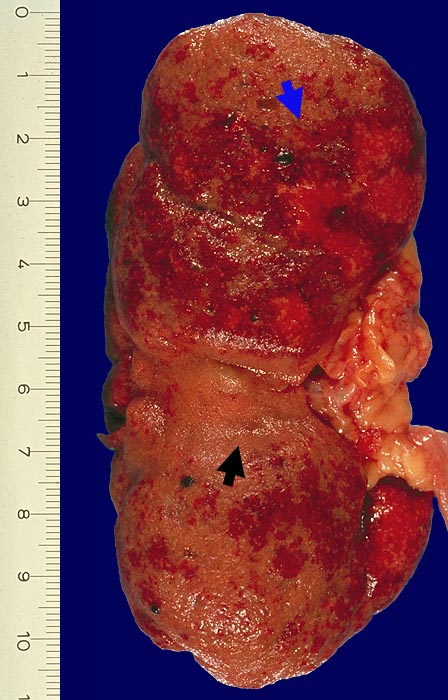

PathoPic ID 1754 - Chronische Pyelonephritis mit akutem Schub

Chronische Pyelonephritis mit akutem Schub

Neben ausgedehnten

Narbenfeldern akute Pyelonephritis mit ausgedehnten, konfluierenden

Eiterherden umgeben von einem hyperämischen Randsaum.

Diabetes mellitus TypII.

Chronische Pyelonephritis bei 8% aller Autopsien. 25% der chronischen Pyelonephritiden mit akutem Schub bei Autopsie.